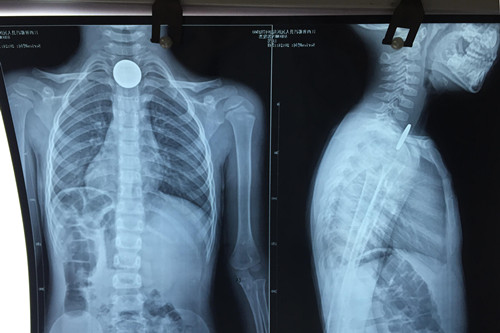

3岁患儿郭某,傍晚时分在家玩耍时口含一枚五角面值的硬币,不慎吞入后反复恶心、呕吐,连喝水都会引发呕吐。就近送至都昌县人民医院行胸片检查,证实硬币嵌顿于食道入口处,建议转上级医院就诊。晚上22:00左右赶到九江市,在专科医院挂急诊就诊,因无对口科室急诊,在其总值班医师的指引下,来到临床医学院/附属医院耳鼻喉科就治。当班医生游锦接诊后,成功取出硬币,稍作观察,患儿于23:30左右离院回家。

对于如何取出硬币,游医生介绍说,小儿食管异物取出比较棘手,例如这位3岁患儿,来院就治时已距误吐硬币达6小时左右,异物刺激强烈,难受哭闹,很难配合治疗。以往这种情况多采用全麻下硬质食管镜取食管异物,患者甚至需住院两至三天。从今年5月以来,临床医学院/附属医院开始利用导尿管来取小儿食管异物这一新方法,现已成功治疗了数十名误吞异物的小朋友。因为导尿管柔软细小,引起咽反射轻微,不会引起患儿的较大恐惧感, 在表麻或者局麻下即能配合,手术安全高效。大部分情况下也不需住院,花费明显减少。